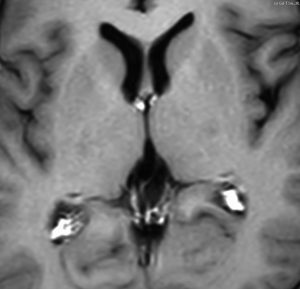

この例は古いので第3脳室開窓術 ETV をしていません。左はICE化学療法前。中央は9日後。右は25日後です。閉塞性水頭症があっても1週間くらいで中脳水道が通って水頭症は改善します。ジャーミノーマであれば,ICE化学療法1コースでかなり縮小するはずです。このような顕著な効果がない時には,逆にジャーミノーマ以外の胚細胞腫瘍が混在していると考えた方がいいでしょう。多くは奇形腫の混在です。